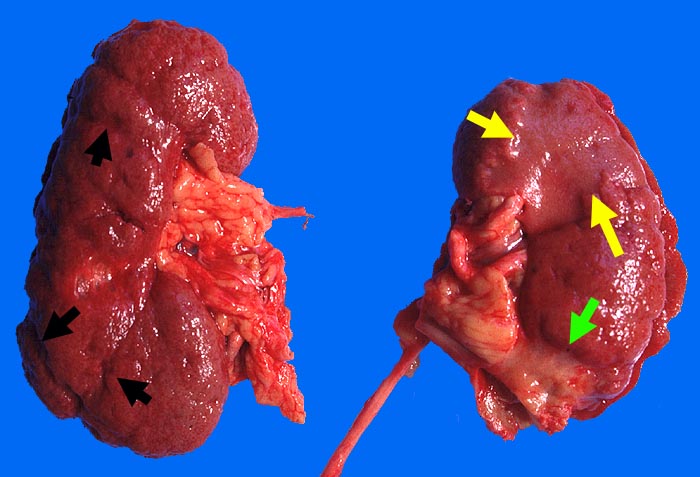

Infarktnarbe, vaskuläre Narben und Subinfarkt

► Niereninfarktnarbe.

► Vaskuläre Nierenrindennarben.

► Subinfarkt.

► Vaskuläre Nierenrindennarben.

► Subinfarkt.

Schwere allgemeine Atherosklerose.

Niereninfarktnarbe und vaskuläre Nierenrindennarben entstehen durch vollständige Okklusion unterschiedlich grosser versorgender Arterien. Der Subinfarkt entsteht bei unvollständigem Gefässverschluss mit Verminderung der Durchblutung. Daraus folgt eine Atrophie und Fibrose des Gewebes, nicht jedoch eine Nekrose.